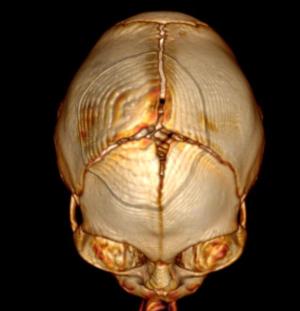

In a third study, ultrasound and fetal MRI were performed on pregnant patients with Zika virus infection at different gestational ages. Once the babies were born, they underwent ultrasound, CT and MRI. The researchers then created 3-D virtual and physical models of the skulls. More than half the babies had microcephaly, brain calcifications and loss of brain tissue volume, along with other structural changes.

"The emergence of Zika virus in the Americas has coincided with increased reports of babies born with microcephaly," said study author Heron Werner Jr., M.D., Ph.D., from the Department of Radiology at Clínica de Diagnóstico por Imagem. "An early diagnosis may help in treating these babies after birth. Moreover, the knowledge of abnormalities present in the central nervous system may give hints about the pathophysiology of the disease."